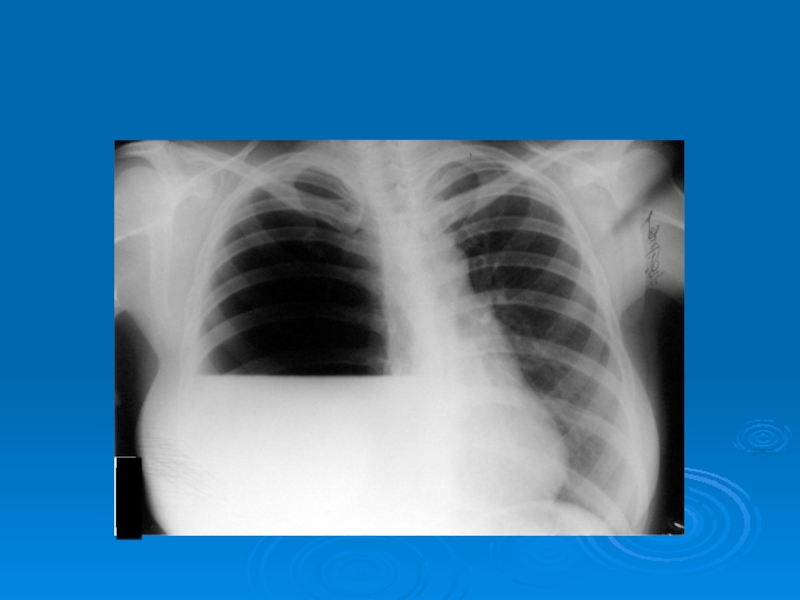

Слайд 39Затемнение части легочного поля (гидроторакс)

Затемнение части легочного поля (гидроторакс)